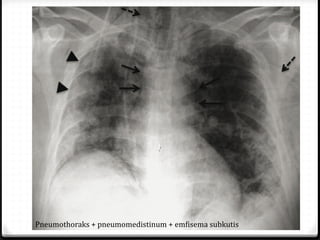

Pneumothoraks

0 Udara pada rongga pleura

0 15%–40% ditemukan pada trauma thoraks

0 Ruptur alveoli karena ada tekanan meninggi secara tiba-tiba

pada intrathorakal akibat trauma dengan atau tanpa fraktur

costae

0 Radigrafi polos >>

0 ± 10% tidak dapat dievaluasi dengan radiografi polos  CT scan

Pneumomediastinum

0 Cedera pada jalan nafas

0 Tingkat kematian tinggi

0 Jarang, 0.2%–8% dari seluruh kasus trauma thoraks

Pneumothoraks + pneumomedistinum + emfisema subkutis